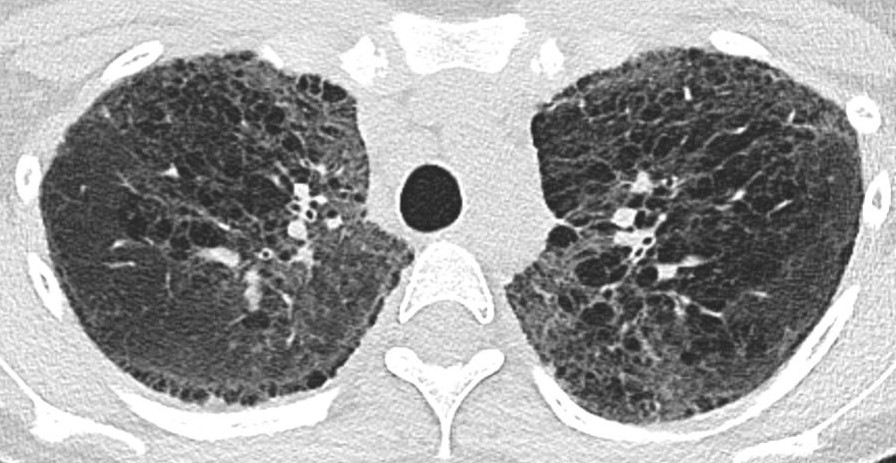

In the phase 3 TETON-2 trial involving patients with idiopathic pulmonary fibrosis, inhaled treprostinil was associated with a smaller decline in forced vital capacity and a lower risk of clinical worsening than placebo over 52 weeks. Full trial results: nejm.org/doi/full/10.10…